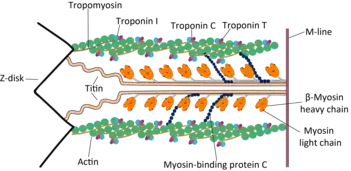

Familial hypertrophic cardiomyopathy is inherited as an autosomal dominant trait which is attributed to mutations in one of a number of genes that encode for the sarcomere proteins, and most diagnosed individuals will have an affected parent. Occasionally, both copies of the gene will be defective, a condition that may lead to a more severe manifestation of the disease.[24][10]

Currently, about 50–60% of people with a high index of clinical suspicion for HCM will have a mutation identified in at least one of nine sarcomeric genes. Approximately 40% of these mutations occur in the β-myosin heavy chain gene on chromosome 14 q11.2-3, and approximately 40% involve the cardiac myosin-binding protein C gene. Since HCM is typically an autosomal dominant trait, children of a single HCM parent have 50% chance of inheriting the disease-causing mutation. Whenever such a mutation is identified, family-specific genetic testing can be used to identify relatives at-risk for the disease, although clinical severity and age of onset cannot be predicted.[25]

Over 1400 mutations have been identified in genes known to lead to HCM.[28] Some mutations could have more harmful potential compared to others (β-myosin heavy chain). For example, troponin T mutations were originally associated with a 50% mortality before the age of 40. However, a more recent and larger study found a similar risk to other sarcomeric protein mutations.[29] The age at disease onset of HCM with MYH7 is earlier and leads to more severe symptoms.[30] Moreover, mutations on troponin C can alter Ca+2 sensibility on force development in cardiac muscle, these mutations are named after the amino acid that was changed after the location in which it happened, such as A8V, A31S, C84Y and D145E.[31]